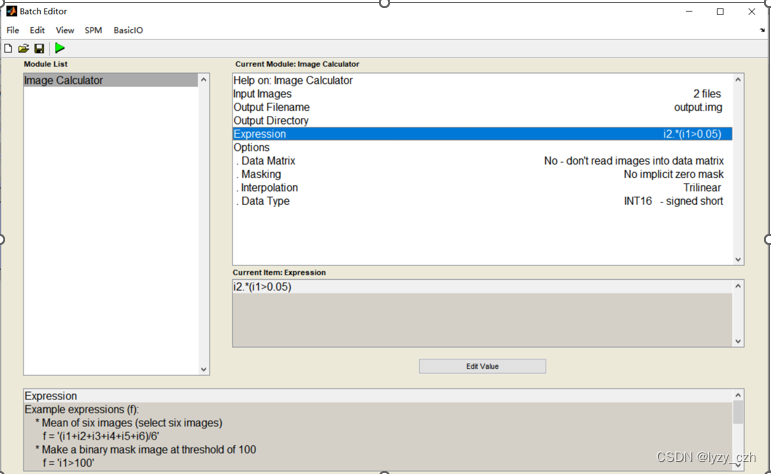

点击ImCalc

弹出如下界面,Input Images先选择MRI的图像,即wmxxxx.nii(也可以选MRI模板),再选rwmeanxxxx.img,Expression输入i2.*(i1>0.05),其中i1表示第一张图像,i2表示第二张,运行后会在matlab的当前路径输出结果,我这里是PETprocess\processing,所以在下面会生成output图像。

注意在Image Calculator的Expression输入是固定的因此可以直接在这里输入如下: